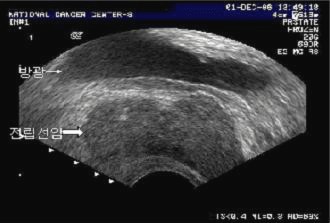

경직장(經直腸) 즉 직장을 통해서 하는 초음파검사(transrectal ultrasound, TRUS)는 직장수지검사로는 확인되지 않는 병변을 발견하고 그와 관련하여 전립선의 용적을 계산하기 위해 시행하며, 정낭(精囊, 정관의 끝에 위치하며 정액을 생산하는 주머니)이나 전립선 피막(皮膜)의 침범 여부를 파악해 국소적 병기를 결정하는 데도 이용됩니다.

하지만 경직장 초음파검사에서 암이 의심되는 경우 중 실제 암으로 확인되는 것의 비율이 낮다는 단점이 있어서, 이를 보완하기 위해 최근에는 혈류 증가를 관찰할 수 있는 색도플러(color Doppler) 초음파검사를 보조적으로 이용하고 있습니다.

전립선암을 진단하기 위한 조직검사는 주로 경직장 초음파의 유도 아래 침생검(針生檢, needle biopsy)을 합니다. 항문을 통해 직장에 초음파 기구를 넣어 전립선을 관찰하면서 전립선을 여러 구획으로 나누어서 각각의 구획에서 조직을 채취해낸 후 병리 검사를 하는 방법입니다. 혈중 전립선특이항원(PSA)검사에서 전립선암이 의심되었으나 경직장 초음파검사에서는 특별한 병변이 보이지 않았을 경우엔 전립선 6~12곳의 조직 생검을 하게 됩니다.

경직장초음파 검사 이미지

[경직장초음파 검사]

전립선암의 직장 초음파 소견 이미지

[전립선암의 직장 초음파 소견]